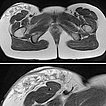

In der transversalen T2-Wichtung, fettunterdrückt, ist die rein epifasziale Ausdehnung der LM im subkutanen Fettgewebe klar zu erkennen. Die darunter liegende Muskulatur ist nicht betroffen.

Beachte in der Ausschnittsvergrößerung (unteres Bild) die exophytische Ausdehnung der mikrozystischen Anteile (stark hyperintens) der LM bis über das Niveau der Haut.

In der gleichen Schichtführung der MRT (oben Übersicht, unten Ausschnittsvergrößerung) in T2-Wichtung ohne Fettunterdrückung sind die gleichzeitig vorhandenen bindegewebigen Anteile der hart tastbaren LM als hypointense netzartige Zeichnung besser zu sehen. Beachte wieder den erhabenen exophytischen Anteil oberhalb des Hautniveaus.